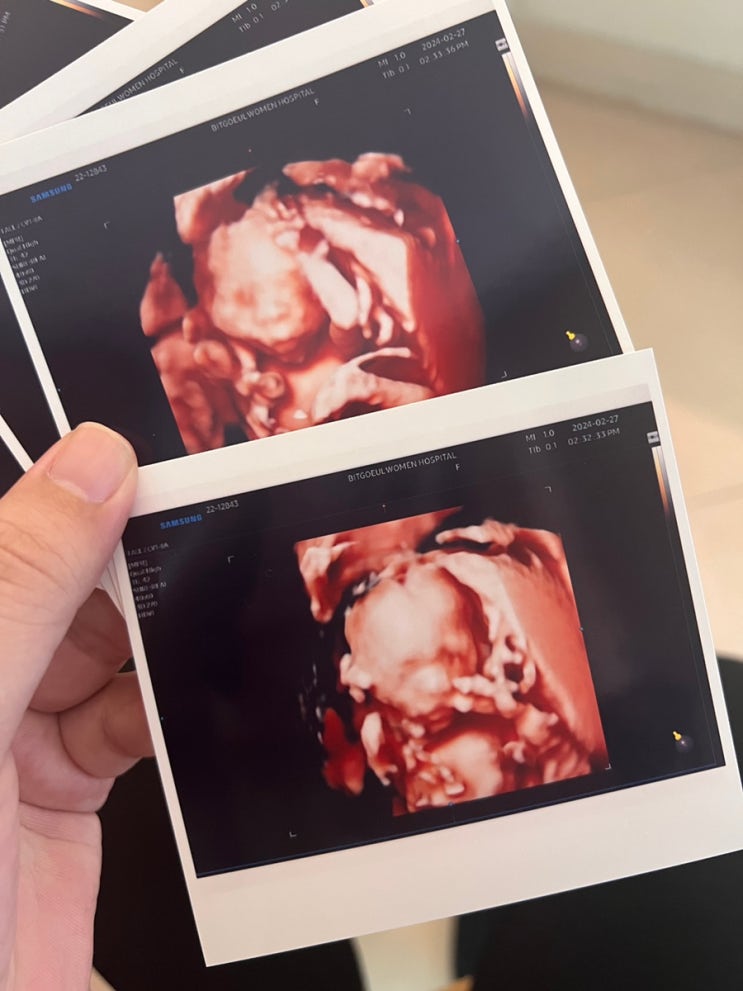

시험관 1차성공 / 프레메디 산부인과 시험관 쌍둥이 부정출혈 입덧시작

저번 글에선 분명 아기집이 하나였는데.. 음.. 그렇죠?? ㅋㅋㅋㅋㅋㅋㅋㅋㅋㅋㅋㅋ 시험관을 하고나서 5주 ...